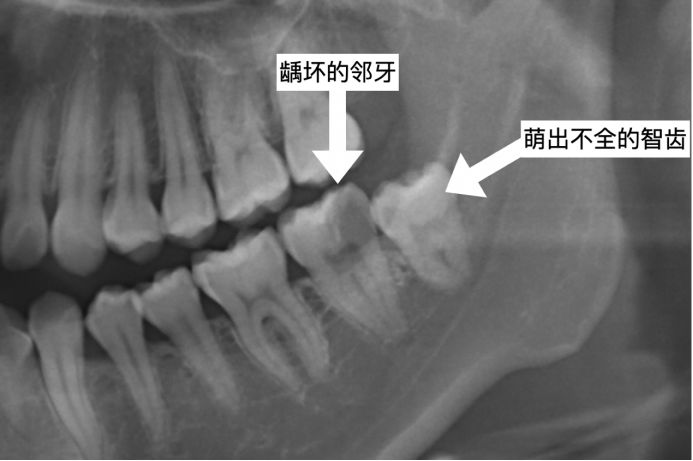

2.损伤邻牙:正如开篇所举的例子,患者多半不自知,是由牙医借助X光片诊断得知。这种情况下,通常智齿萌发的空间不足,因而会横向向前生长,倒在第二磨牙旁边,从而造成第二磨牙清洁不易,甚至是牙齿部分吸收的现象,导致患者疼痛不适。这时建议尽快拔除,不然两颗牙后期一个都别想留住。